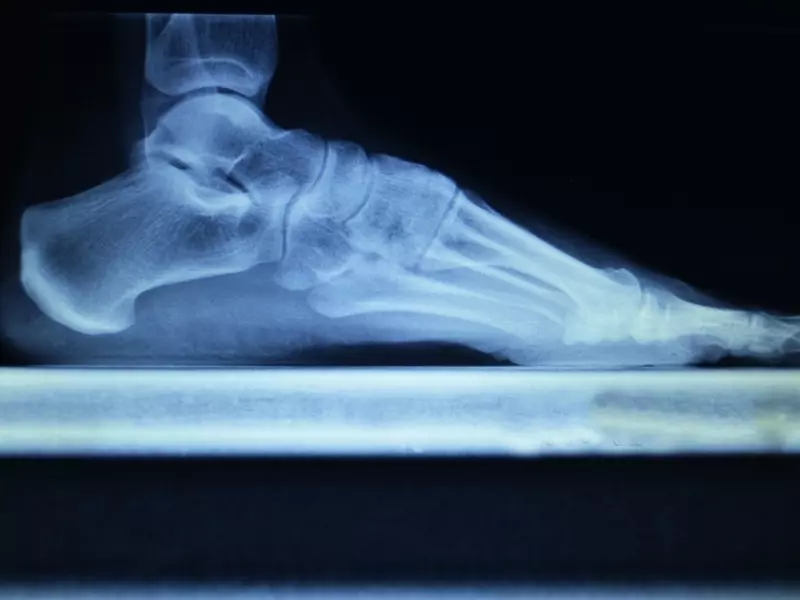

Efekty zabiegów IS, polegającej na bardziej funkcjonalnym ułożeniu ciągów mięśniowo powięziowych względem pionowej osi ciała, będą najlepiej widoczne u osoby intensywnie „używającej” ciało. Mówiąc precyzyjniej – od pacjenta uprawiającego sport, atlety czy biegacza można spodziewać się lepszego przyjęcia i reakcji ciała na głęboką pracę na płaszczyznach powięzi i w przegrodach międzymięśniowych. Można również zakładać, że wszelkie uwolnienia tkanek i ich biomechaniczne konsekwencje na całą strukturę będą bardziej wyraźnie widoczne u biegacza niż u osoby prowadzącej siedzący tryb życia, jako że trenujący biegacz natychmiast musi przyswoić i zareagować na wprowadzone zmiany.